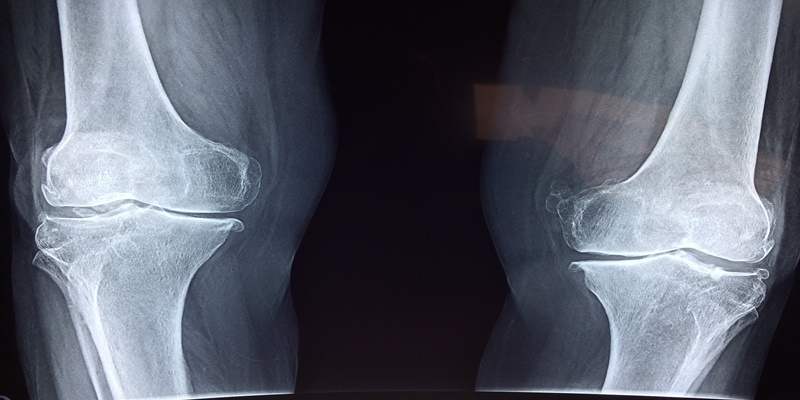

특별한 경우를 제외하고는 일반적으로 나이가 들어감에 따라 뼈가 약해지고, 골다공증으로 고생을 하시는 분들이 많이 늘어납니다. 한순간에 뼈를 건강하게 만들 수는 없으나 운동과 식이요법으로 점차적으로 뼈를 강하게 할 수는 있습니다.

뼈가 약해지는 가장 큰 요인은 노화지만, 20~30대 젊은 여성의 경우 다이어트나 운동 부족으로 골밀도가 떨어져 뼈가 약한 경우도 많습니다. 또한, 갑상선 기능 항진증이나 천식, 류머티즘성 관절염 등의 질병을 앓았거나 스테로이드제를 과도하게 사용해 골밀도가 낮아지면 골절이 쉽게 올 수 있습니다.